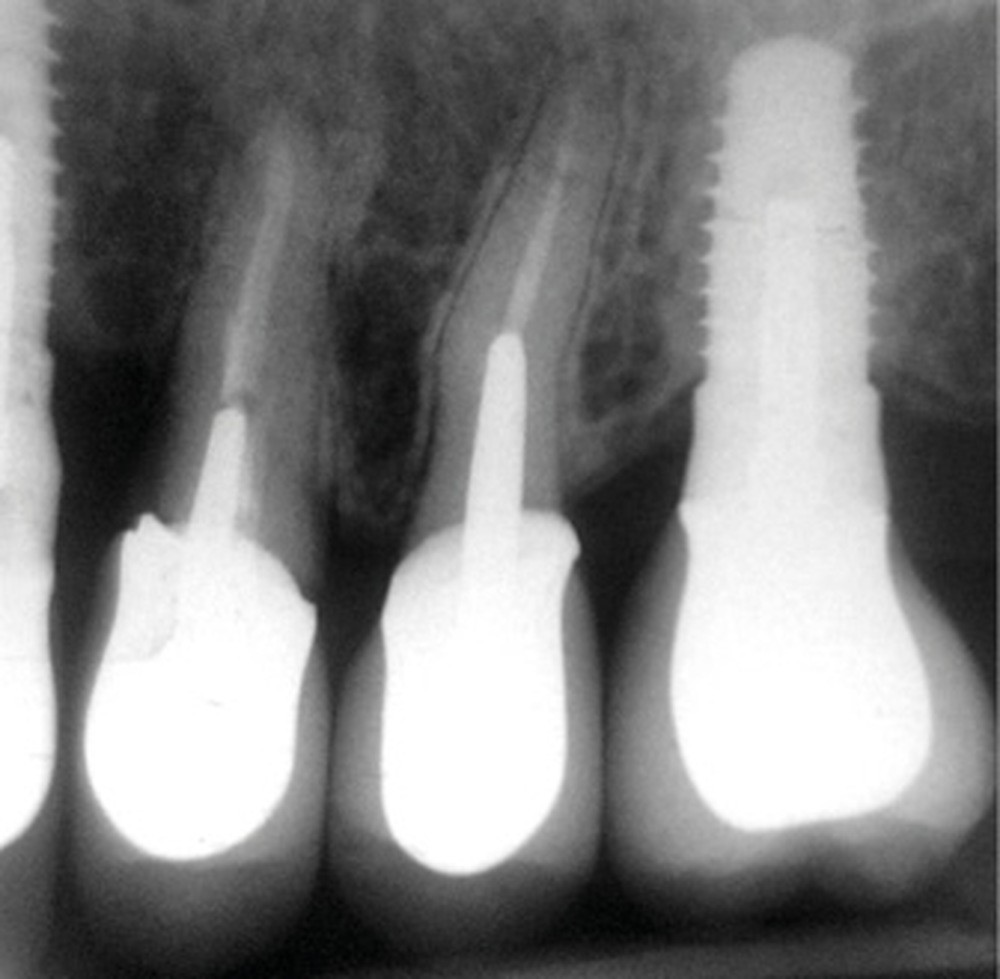

Une patiente de 64 ans, en bonne santé générale, suivie en maintenance parodontale depuis sept ans (parodontite 3B), est vue en juin 2014 pour l’extraction de sa 24 en raison d’infections endodontiques récurrentes. Le plan de traitement prévoit la pose extemporanée d’un implant et sa restauration prothétique quatre mois plus tard. La 25 est une dent couronnée et 23 et 26 sont des restaurations implantaires (fig. 1a à c). La dent antagoniste 35 est une restauration implantaire.

La radiographie péri-apicale au long cône confirme, sur la 25, un élargissement desmodontal, notamment en distal, des niveaux osseux mésio-distaux réduits par rapport aux clichés de contrôle précédents (les radiographies sont réalisées avec une technique parallèle avec des angulateurs de Rinn non personnalisés), un apex radiculaire normal et des niveaux osseux stables sur les implants adjacents (fig. 5). Le cisaillement systématique du fil dentaire lors de son passage confirme des points de contact très étroits entre 24, 25 et 26.